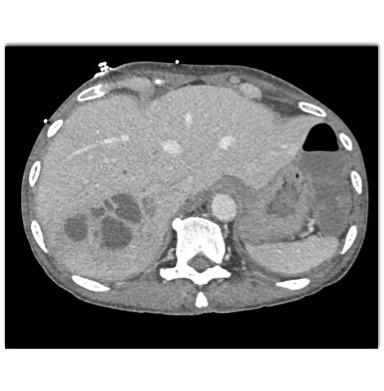

In this HIV patient with an FUO the best dx is ?

liver abscess and diverticulitis